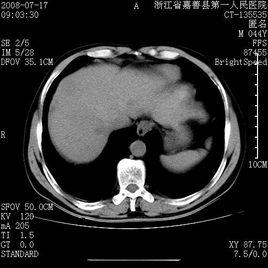

增強掃描就是把藥從靜脈(一般為肘前靜脈)注入血管內同時進行CT掃描,可以發現平掃(沒有向血管內注藥掃描)未發現的病灶,主要用於鑑別病變為血管性或非血管性,明確縱膈病變與心臟大血管的關係,了解病變的血供情況以幫助鑑別良、惡性病變等。增加病灶的信息量,以便於對病灶定性分析甚至明確診斷.

CT檢查是眾多醫學影像診斷技術中的一種,其診斷疾病的一個特點就是測量X射線通過人體後的衰減值,反應X射線衰減值的專業術語為密度,CT診斷學上用“CT值”來描述密度的差異。相同的組織結構應是相同的密度,也就是說正常的組織器官如肝臟的密度是比較均勻的。但是某些病變如腫瘤,其生長在正常的組織器官中,早期因數目少、體積小,當採用普通CT掃描時,腫瘤組織與周圍的正常組織可以表現為相同或相似的密度,這樣CT醫生往往因無法發現病變而報告正常。但若此時再行增強掃描(指靜脈注射造影劑後的掃描),病變部位可發現異常的強化現象,從而與正常的組織區分開來,這樣就可以早期發現病變,及早進行科學、合理的治療,既可以治癒疾病,又可降低治療費用。因此,增強掃描絕非“多此一舉”,應積極配合醫生的檢查,以免留下不可挽回的遺憾。